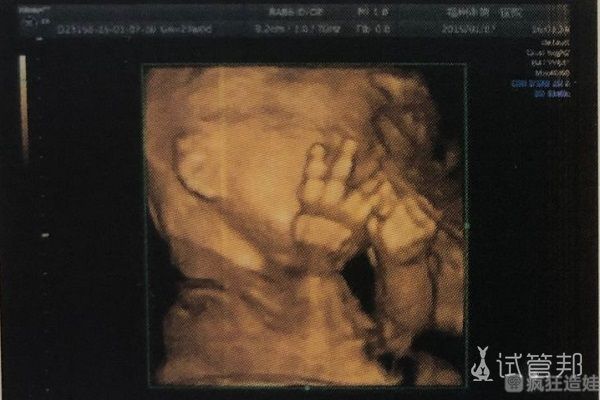

孕13周,在羊穿前做了四维大排畸,我当时的想法是如果胎儿肢体有缺陷就直接尽早做流产,好在检查结果都没有什么大问题。如果智力有问题通过B超也看不出来,提前预约了羊穿手术,等时间到了就上医院。